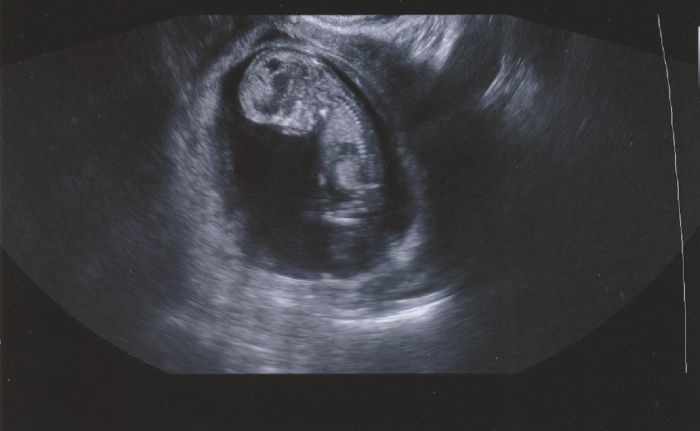

A ještě dodatečně přikládám našeho drobečka ze screeningu ve 12tt